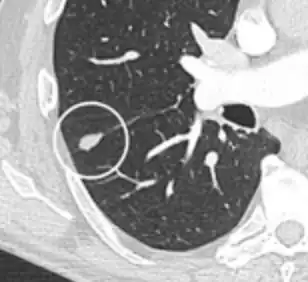

- In case of subsolid nodules, being part solid has a higher risk of cancer than being purely ground glass opacity.

-

Part solid nodule.[9] -

Ground glass opacity nodule.[9]